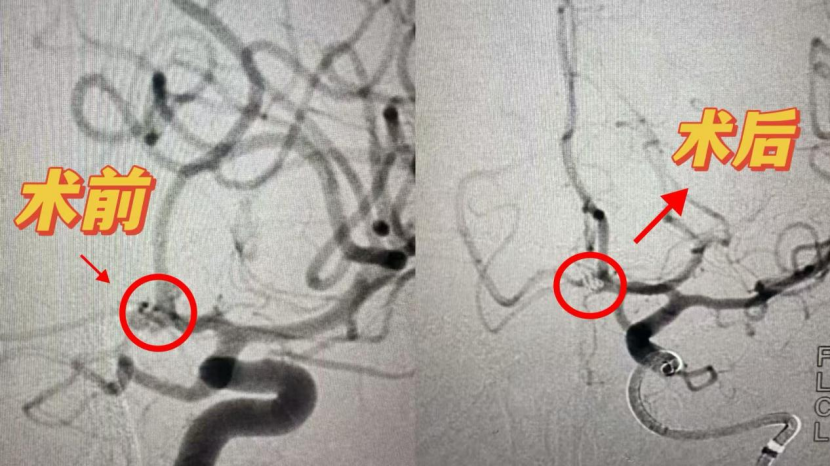

守护生命质量:济南南郊医院康复科助脑动脉瘤患者重建生活尊严

十月下旬,济南南郊医院脑科成功为一位因脑动脉瘤破裂并发脑疝的李阿姨(化名)实施了紧急手术。如今,在康复科的治疗室里,另一场关乎生命质量的“战役”正悄然展开。